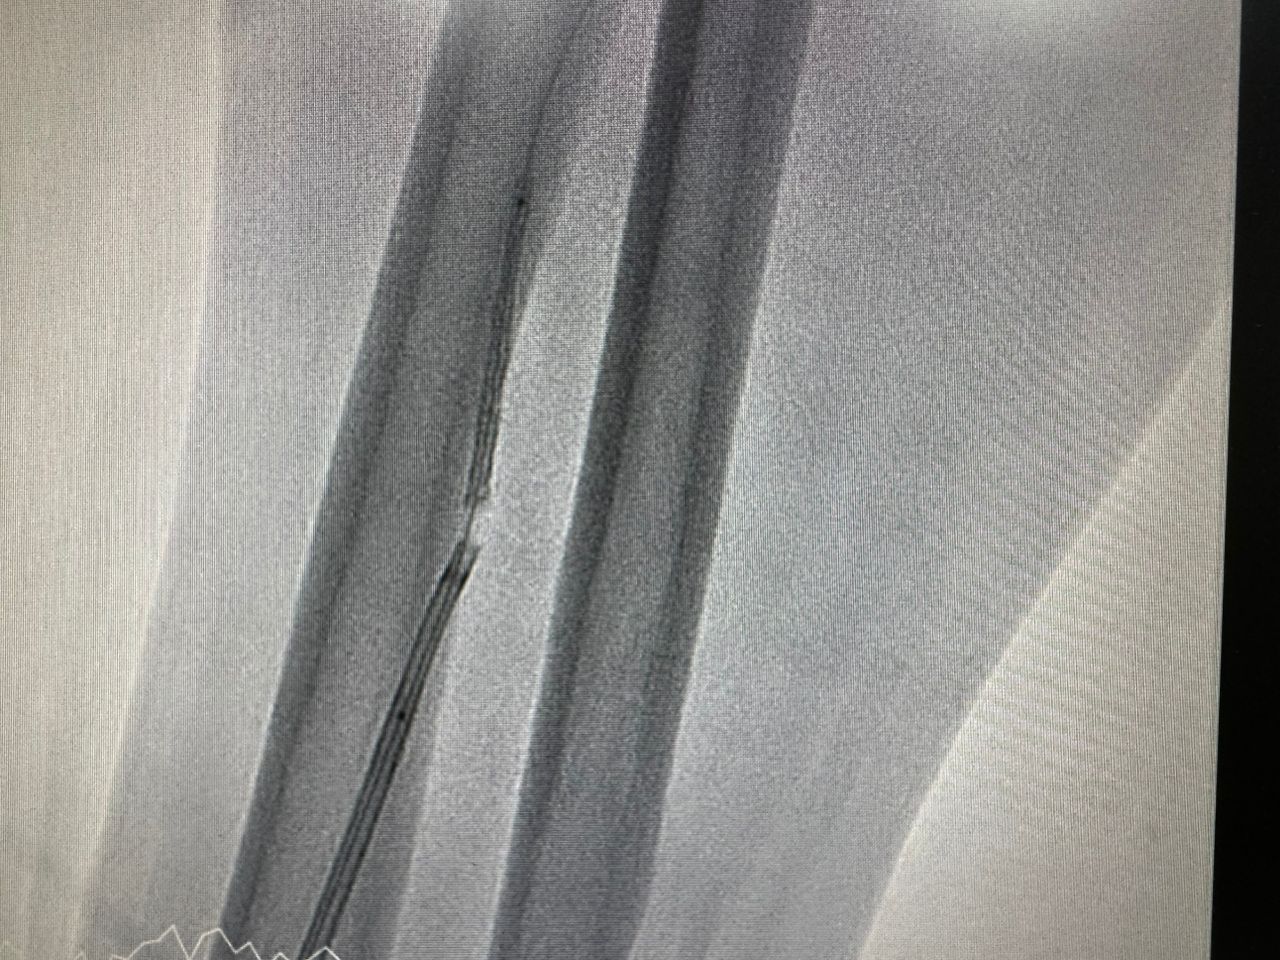

6Fr Guiding catheter JR 3.5 was used to engaged the rightcoronary artery and lesions was crossed with guidewire sion blue. Predilatationof lesions was performed sequentially with a 4.0 x 15mm non-compliant balloonthen 4.0 x 15mm scoring balloon, resulting in adequate lesion expansion andTIMI 3 flow. We proceeded to stent the mid to distal segment of RCA with 4.0 x36mm drug eluting stent. Subsequently attempted to stent the ostial to midsegment of RCA with 4.0 x 48mm durg eluting stent but while trying to readjustposition of stent, we were unable to withdraw the undeployed stent into theguiding catheter. Noted proximal stent edge crumpled at the mouth of guidingcatheter and stent balloon was retracted half into the guiding catheter. The whole system was pulled back into theradial artery where the stent balloon was pulled out of guiding catheter. Withthe stent still remained on the coronary guidewire, an amplatz gooseneck snarewas inserted. The crumpled stent was successfully snared out. Percutaneous coronary intervention to RCA was continued withreengagement with 6Fr JR 3.5 and lesion crossed with guidewire runthroughfloppy. A 4.0 x 48mm drug eluting stent was deployed at ostial to mid RCA andpost dilated stent with 4.0 x 18mm NC balloon. Ostial flare of RCA was donewith 4.5 x 15mm NC balloon. Final angiogram showed well expanded stent withTIMI 3 flow. No perforation or dissection noted.

Case Summary